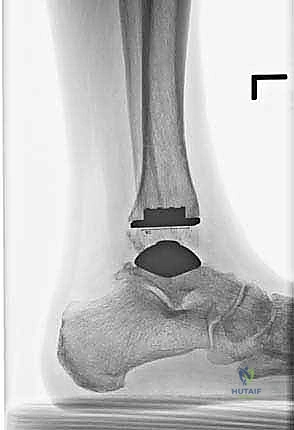

تتكون غرسة STAR من ثلاثة أجزاء رئيسية ولا تستخدم الأسمنت العظمي (Cementless)، بل تعتمد على النمو العظمي الدقيق داخل مسام الغرسة لتثبيتها بشكل دائم:

- المكون الظنبوبي (Tibial Component): صفيحة معدنية مسطحة من سبائك الكوبالت والكروم (Cobalt-Chromium)، تُثبت في أسفل عظمة الساق (الظنبوب) بواسطة أسطوانتين معدنيتين تدخلان في العظم لضمان الثبات المطلق.

- المكون الكاحلي (Talar Component): قطعة معدنية تغطي قبة عظم الكاحل، مصممة بشكل تشريحي منحني يحاكي تماماً شكل العظمة الأصلية، وتحتوي على أخدود طولي.

- الحشوة البلاستيكية المتحركة (Mobile Polyethylene Bearing): هذا هو سر نجاح غرسة STAR. هي قطعة من البلاستيك الطبي عالي الكثافة (UHMWPE) توضع بين القطعتين المعدنيتين. هذه القطعة ليست ثابتة، بل تنزلق بحرية للأمام والخلف، وتسمح بدرجة طفيفة من الدوران. هذا التصميم "المتحرك" يقلل بشكل هائل من إجهاد القص (Shear Stress) على واجهة العظم والمعدن، مما يقلل من احتمالية تخلخل الغرسة (Loosening) على المدى الطويل، ويمنح المريض نطاق حركة فسيولوجي مذهل.